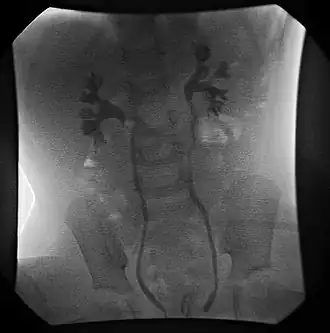

Cystographie mictionnelle retrouvant un reflux bilatéral grade III

La cystographie mictionnelle consiste en l'opacification de la vessie par un produit de contraste qui est introduit par la montée d'une sonde dans la vessie par l'intermédiaire de l’urètre. Des clichés radiologiques sont alors pris. Normalement les uretères ne sont pas visualisés, sauf en cas de reflux. L’urocystographie rétrograde est une exploration dynamique qui doit toujours comporter un cliché pendant une miction à plein jet et un cliché post mictionnel afin de mettre en évidence les reflux purement actifs et d’éliminer un obstacle cervico-urétral. La cystographie permet d’affirmer l’existence d’un reflux, d’affirmer son caractère primitif idiopathique. Elle permet de distinguer le reflux passif survenant au cours du remplissage, d’un reflux actif ne se manifestant que pendant la miction. Plusieurs classifications ont été proposées. La classification internationale de Duckett[6] comporte cinq stades :

Type I : reflux dans un uretère pelvien fin.

Type II : reflux total sans dilatation urétéro-pyélo-calicielle.

Type III : dilatation urétéro-pyélique modérée sans atteinte calicielle.

Type IV : dilatation urétéro-pyélo-calicielle avec bombement et déformation des papilles.

Type V : dilatation et tortuosité urétérale majeure, grosse dilatation pyélo-calicielle avec perte de la vision des papilles.

Il faut ajouter à ces 5 stades la notion du reflux intra-rénal qui peut être présent dans les stades IV et V et apparaît comme un facteur de gravité. Enfin, la cystographie peut montrer l’existence d’autres anomalies vésicales associées. Le « trapping » consiste en une rétention de produit opaque dans l’uretère témoignant d’une hypotonie majeure de l’uretère, soit d’un certain degré d’obstruction au niveau de l’uretère terminal. Ce phénomène est un facteur aggravant. Une cystographie normale ne permet pas d’éliminer un reflux.